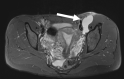

Objective: Acetabular paralabral cysts are common and are almost always associated with labral tears. Uncommonly, they extend into the periacetabular soft tissues or may propagate along peripheral nerves causing pain and hip dysfunction. The aim was to evaluate the clinical and MRI presentations of such cases including perineural propagation.

Results: 14 cases were recorded. The mean age was 56.9 years (range = 30-79 years) and female:male ratio was 1:2.6. The commonest presenting complaint was hip pain (10/14, 71.4%). Other complaints included groin pain, perineal pain and hip dysfunction. No symptoms were attributed to the acetabular paralabral cyst in 3/14 patients (21.4%). None had foot drop. The cysts were multilocular in all cases and were homogenously T2 hyperintense in 13/14 (92.9%). Labral tears were identified in 11/14 cases (78.6%). The sciatic nerve was most commonly involved in 5/14 cases (35.7%) with the obturator, medial femoral cutaneous nerve, femoral nerve, superior and inferior gluteal nerves also affected.No intervention was undertaken in 9/14 cases (64.3%). 5/14 (35.7%) underwent image guided aspiration and corticosteroid injection. 4/5 such patients reported reduced pain following the procedure.

Conclusion: Paralabral cysts demonstrating perineural propagation are uncommon and exhibit varied presentations. Most patients who underwent image-guided or surgical interventions reported an improvement in symptoms.